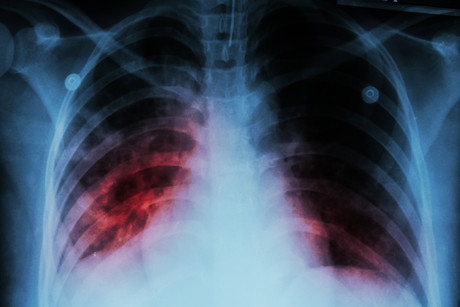

As explained by Professor Stow, chronic inflammatory diseases occur when inflammation cannot be effectively switched off, leading to recurrent damage to organs such as the lungs. “Inflammation is typically launched to ward off infection or danger, then subsequently curtailed to avoid ongoing tissue damage,” she said.